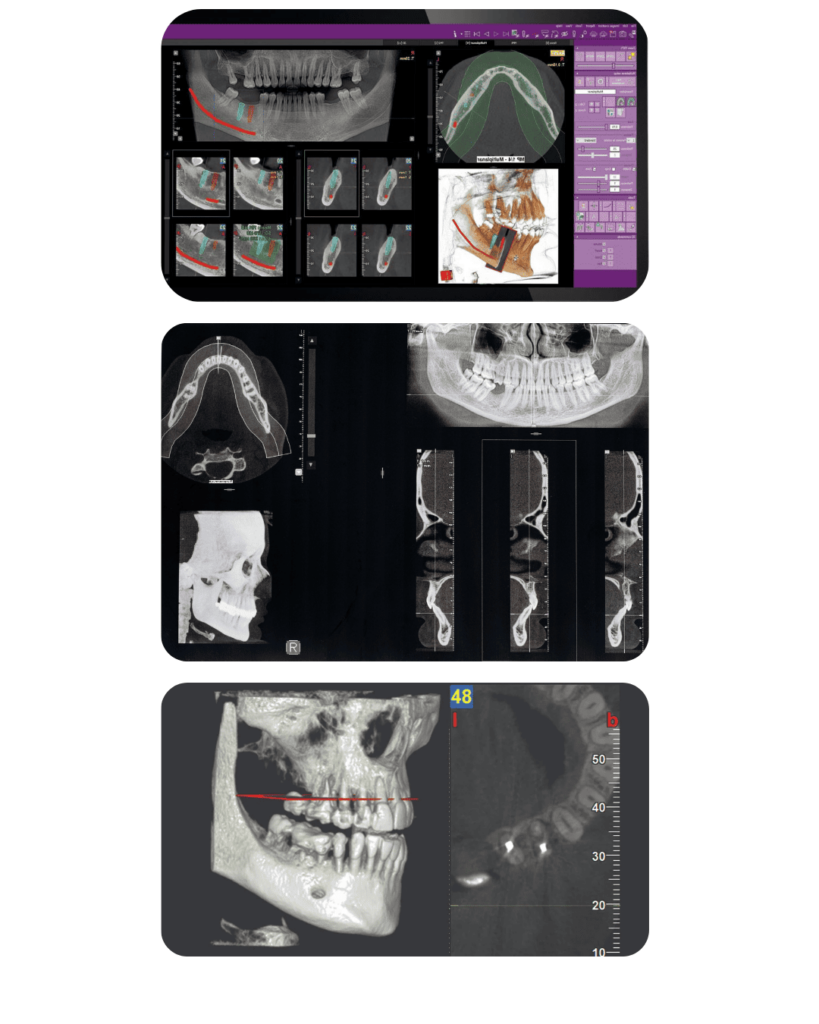

CBCT

(3D DIJAGNOSTIKA)

CBCT pruža 3D prikaz zuba, kosti i mekih tkiva uz visoku rezoluciju. Nezamjenjiv je pri planiranju implantoloških, oralno-kirurških, endodontskih i složenih dijagnostičkih zahvata, jer omogućuje maksimalnu preciznost i predvidljivost terapije.